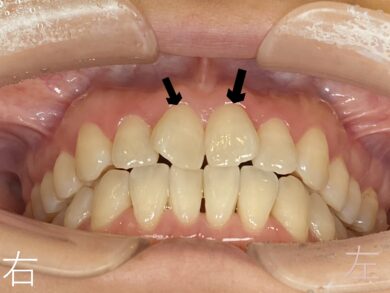

上顎および下顎の前歯のゆがみ【叢生】を主訴に来院されました40代女性の方の症例を紹介させていただきます。

下記写真をご覧ください。

上顎左右前歯部(黒色矢印の歯)のゆがみ【叢生】が確認できます。